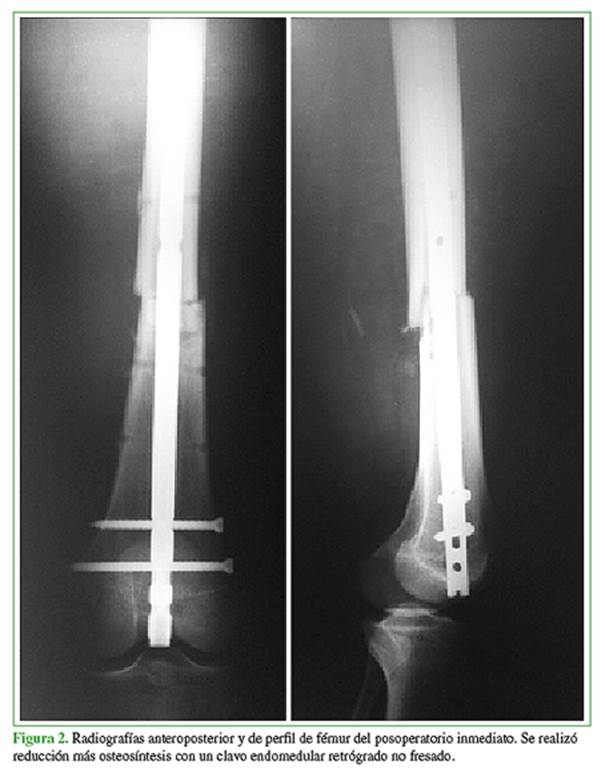

Varón de 17 años de edad que ingresó por un politraumatismo a causa de un accidente de moto contra un automóvil, en el que sufrió una fractura transindesmal de tobillo izquierdo y una fractura de fémur derecho, tipo 32A2 de la clasificación AO, asociadas a un trauma de tórax (Figura 1).

Inicialmente la fractura de fémur se estabilizó con un tutor externo y la fractura de tobillo, con una valva de yeso. Al octavo día se realizó la conversión del tutor externo a clavo endomedular retrógrado de fémur de 9 mm x 350 mm no fresado (Figura 2).